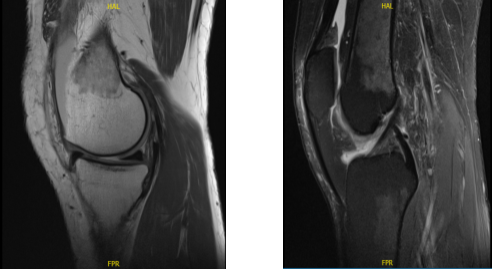

MRI was performed, reviewed and discussed by the doctor; the findings stated the Collateral Ligaments: The medial collateral ligament is intact. The lateral collateral ligament, biceps femoris tendon, iliotibial band, and popliteus tendon is intact.

Cruciate Ligaments: The anterior and posterior cruciate ligaments are intact. Menisci: The medial meniscus is intact. The lateral meniscus is intact. The Cartilage: There is a 9 x 6 mm full-thickness chondral defect in the midportion of the medial femoral condyle.

The chondral surfaces in the lateral compartment are intact. There is a focal area of chondral fissuring and partial-thickness cartilage loss in the central trochlea. Bones: The visualized osseous structures demonstrate normal bone marrow and cortical signal intensity without evidence of fracture, trabecular bone injury or dislocation.

No osseous lesions are identified. The Extensor Mechanism: The quadriceps and patellar tendons are normal. Joint: Large knee joint effusion. The soft tissues are otherwise normal. The neurovascular structures demonstrate normal course.

It has an impression of 9 x 6 mm full-thickness chondral defect in the midportion of the medial femoral condyle. Focal area of Chondral fissuring and partial-thickness cartilage loss in the central trochlea. Intact medial and lateral meniscus.

MRI-3T Left knee non-contrast